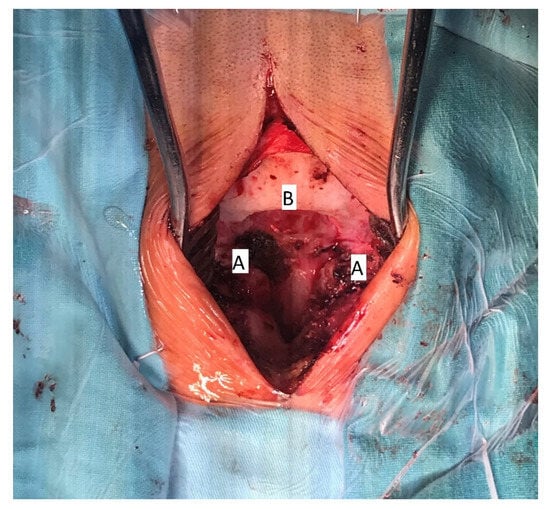

1.3. Surgical Treatment and Early Follow-Up

The patient underwent surgical treatment under general anesthesia and in a prone position. The surgical approach was performed in the mediosagittal plane. The foramen magnum was decompressed with a micro-technique using a high-speed drill and a rongeur (Figure 4). The bony part of the bifid lamina and occipital bone were extremely soft. The bifid arch of the C1 vertebra was covered with the fibrous band which was cut as a part of posterior decompression. An adequate decompression of CCJ and regular closure of the wound was obtained.

Figure 4. Intraoperative image of decompressive craniotomy (B); bifid arch of the atlas (A), 15 years of age.